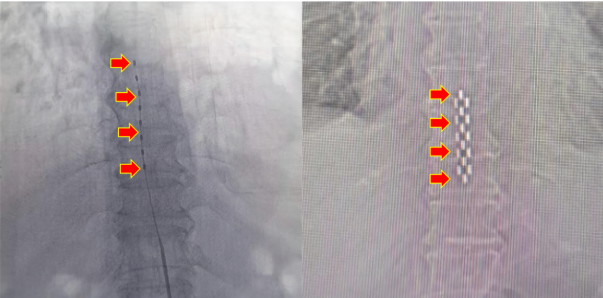

臨時刺激電極(左)  VS 永久刺激電極(右)

術(shù)前(左) VS 術(shù)后(右)

最初神經(jīng)外科予以臨時脊髓電刺激治療,患者左足血供明顯好轉(zhuǎn),創(chuàng)面加速愈合、結(jié)痂。在臨時治療效果顯著的情況下,予以二期手術(shù),植入永久刺激器。術(shù)后患者疼痛明顯緩解,缺血情況顯著好轉(zhuǎn),成功保肢。日前,患者恢復(fù)順利,患者及家屬對治療效果表示滿意。